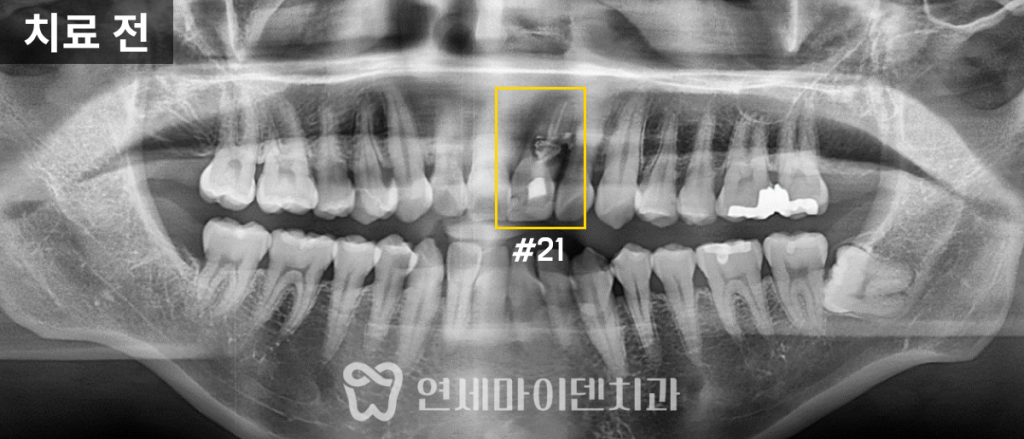

환자분의 치아 방사선 사진을 살펴보면

뿌리쪽 뼈가 까맣게 녹았고, 옆쪽으로 빠져나간 약제도 보입니다.

뼈도 이미 많이 녹았고 염증도 심해서

재신경치료만으로는 회복이 어려울 것으로 보였습니다.